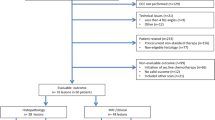

Twenty-one children and young adults (13 males; mean age, 8.6 ± 5.2 years; range, 1–19 at initial diagnosis) with either newly diagnosed (n = 5) or pretreated (n = 16) CNS tumors were retrospectively analyzed. All patients had previously undergone neuro-oncological work-up including cranial magnetic resonance imaging. In all cases, [18F]FET-PET was indicated in a multidisciplinary team conference. The impact of PET imaging on clinical decision-making was assessed. Histopathology (n = 12) and/or clinical and imaging follow-up (n = 9) served as the standard of reference.

This retrospective analysis included 21 consecutive pediatric and adolescent patients with primary CNS tumors (mean age, 8.6 ± 5.2 years; age range, 1–19 at initial diagnosis; and mean age, 12.6 ± 5.6; age range, 2–23 at PET scan date) who underwent [18F]FET-PET for further diagnostic work-up between July 2010 and October 2018 at the Department of Nuclear Medicine at University Hospital Würzburg, Germany. The general cut-off for patient age was 18 at initial diagnosis. One older patient was included as she was diagnosed with a typical pediatric brain tumor (pilomyxoid astrocytoma of the optic pathway) at the age of 19 (patient #11). Five patients presented with newly diagnosed gliomas, while the remaining 16 subjects with primary brain tumors were referred due to equivocal MRI diagnosis.

A total of 21 pediatric and adolescent patients with primary CNS tumors were included (mean age, 8.6 ± 5.2 years; median age 8; range, 1–19 at initial diagnosis; and mean age, 12.6 ± 5.6; median age 14; range, 2–23 at PET scan date). PET and MRI scan were performed within a median of 14 days (range, 5–70 days). Five patients presented with newly diagnosed gliomas, and sixteen children/adolescents were referred with pretreated brain tumors (3 patients with surgery alone, 7 patients with combined surgery and radiochemotherapy, 2 patients with combined surgery and chemotherapy, 3 patients with radiochemotherapy, and 1 patient with chemotherapy alone). In patients who had received combined radiochemotherapy, [18F]FET-PET scans were performed more than 12 weeks from cessation of radiotherapy (median, 31 months; range, 3–141 months).

Six patients presented with low-grade gliomas (pretreated WHO III anaplastic astrocytoma, at the time point of imaging graded as WHO I pilocytic astrocytoma, n = 1; WHO grade I pilocytic astrocytoma, n = 2; WHO grade II pilomyxoid astrocytoma/optic pathway glioma, n = 1; radiological diagnosis of low-grade glioma, n = 2) and 15 subjects with high-grade tumors, distributed as follows: WHO grade III anaplastic astrocytoma (n = 4, one of them as second malignancy after initial treatment of a germ cell tumor), WHO grade III anaplastic ependymoma (n = 1), WHO grade IV diffuse intrinsic pontine glioma (DIPG, n = 2) (neuroradiological diagnosis, one as a second malignancy after initial treatment of a medulloblastoma), WHO grade IV CNS primitive neuroectodermal tumor (n = 1), WHO grade IV ependymoblastoma (n = 2), and WHO grade IV glioblastoma (n = 5). Detailed patient characteristics are summarized in Table 1.